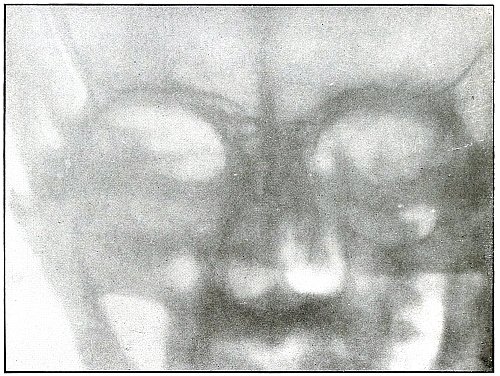

Rifle—Plate 2.

HEAD.

Gunshot Wound of the Head, with Lodgment of the Missile.

Wound of entrance, near outer canthus, with course through eyeball to ethmoid body.

Wound of exit, none.

The Bulgarian Mannlicher bullet, shown half actual size on the plate, must be inclined on its long axis, about 30° from the perpendicular, to the plane of the plate.

The slight penetration of the missile and its normal character show that, having struck no intervening object, it indicted the wound at extreme range.

The treatment should meet the indication for removal of missiles in all superficial or easily accessible locations and when they cause reaction.

Results to be expected are favorable except for loss of the eye. [Pg 16]